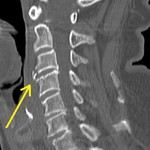

[画像診断]2010-10-08に提示した症例のMRI(頚髄損傷) 2010-10-10

[画像診断]中~下位頚椎損傷による脊髄損傷の分類 2010-10-08